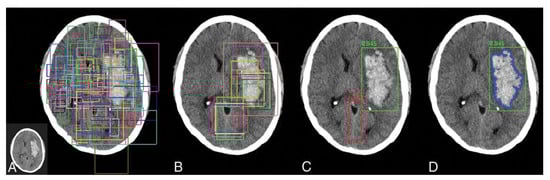

- Wu, Y.; Wang, Z.; Ripplinger, C.M.; Sato, D. Automated object detection in experimental data using Ccmbination of unsupervised and supervised methods. Front. Physiol. 2022, 13, 805161. [Google Scholar] [CrossRef] [PubMed]